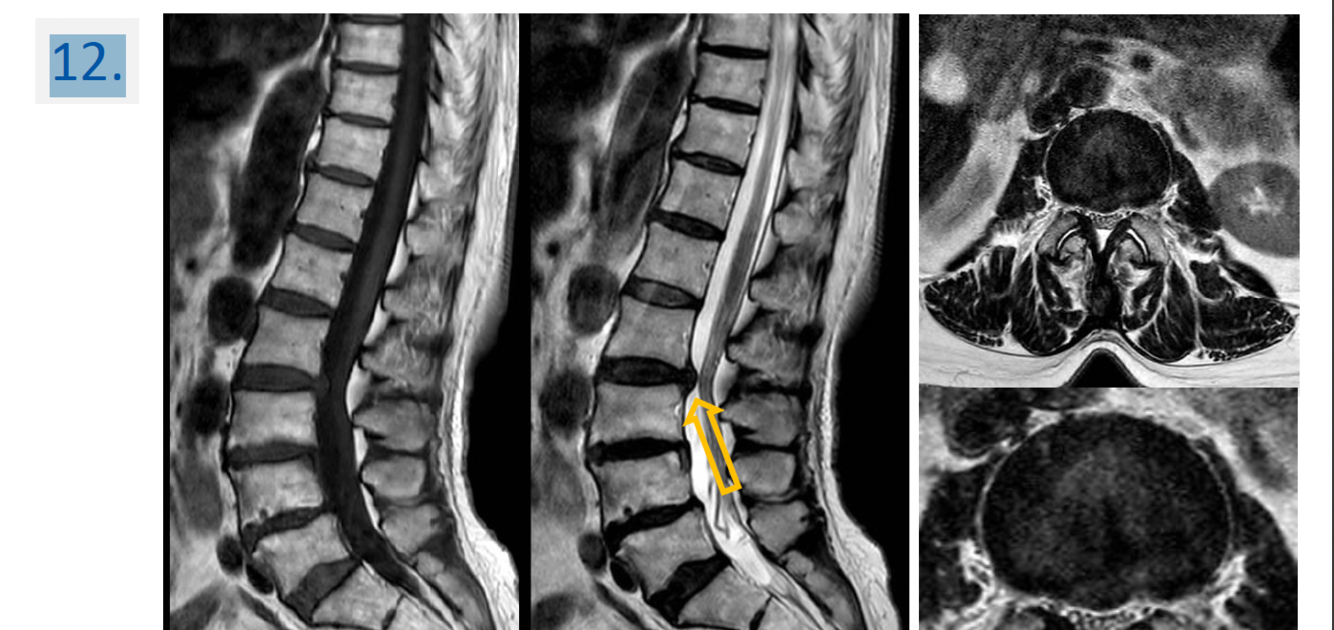

12.